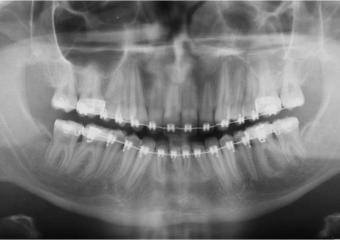

Raio x inicial